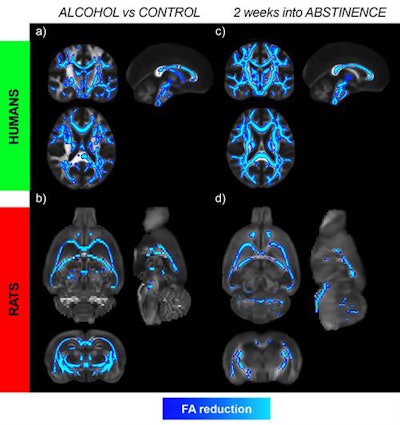

"We found that at two and six weeks of abstinence, the microstructural changes progressed with further decrease of fractional anisotropy and increase of radial diffusivity in humans and rats," wrote first author Silvia De Santis, PhD, from the Institute of Neuroscience CSIC-UMH in Alicante, Spain, and colleagues. "These results challenge the conventional idea that the microstructural alterations start to revert to control values immediately after discontinuing alcohol consumption and provide insights into the neuroadaptations occurring during abstinence."

When the researchers reviewed the DTI results during the weeks of abstinence, they observed widespread microstructural abnormalities, such as reduced fractional anisotropy and axial diffusivity and increased mean and radial diffusivity, among men with alcohol use disorder, compared with the controls. The differences were most notable in the white-matter tracts of the corpus callosum and fornix/fimbria. That finding alone contradicts the conventional idea that the brain begins to return to normal function immediately after the start of abstinence.